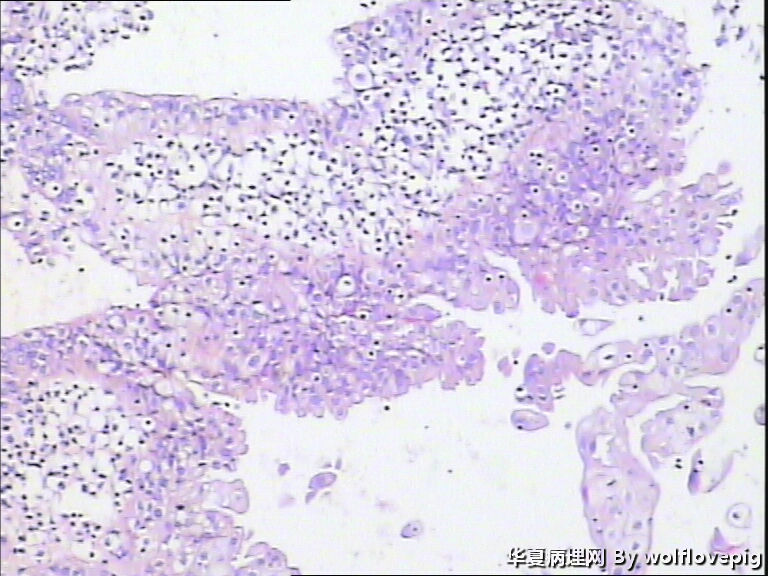

40y,阴道不规则流血10+天